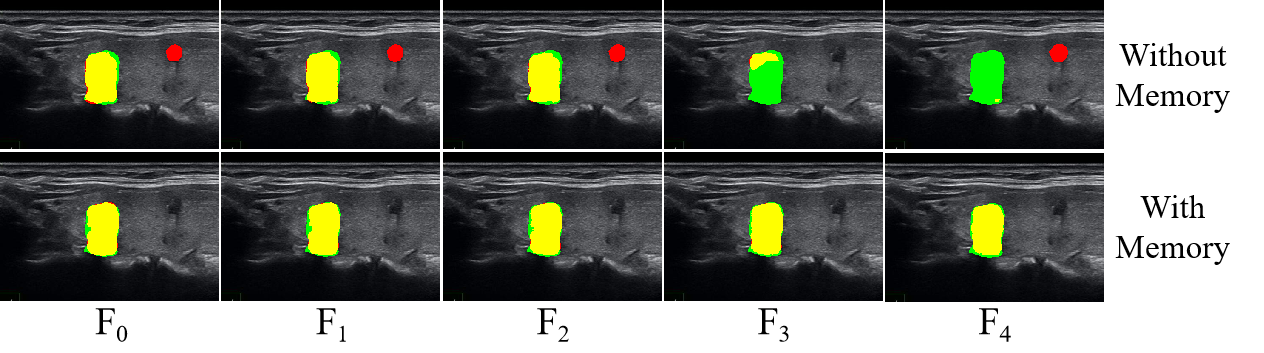

The visualization results with ten frames interval for adding (with memory) and removing (without memory) long short-term memory bank are shown in Fig. 9, highlighting the enhanced temporal tracking capability for long video. It indicates that adding the memory bank can effectively improve blurred boundaries and confusing locations, especially long-range segmentation object tracking. The visualization results of adjacent five frames for adding (with memory) and removing (without memory) long short-term memory bank are shown in Fig. 10. It can be observed that the results without memory exhibit noticeable boundary jitter, whereas the inclusion of memory effectively maintains temporal consistency and mitigates large segmentation discrepancies between adjacent frames.